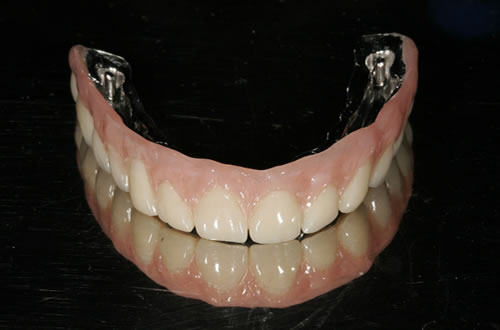

Für den zahnlosen Ober- und Unterkiefer werden dies häufiger Stegkonstruktionen oder Teleskopversorgungen sein (Abb. 8.8 bis 8.16).

Abb. 8.13: Abnehmbare, grazile Brücke.